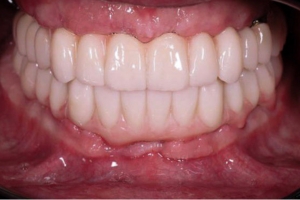

✅ встановлення тимчасових коронок зубів в день чи майже в день операції.

✅ приємний пріродний виглядмзубів, але при різних протоколах є питання “рожевої естетики”.

✅ швидкий та довготривалий результат.